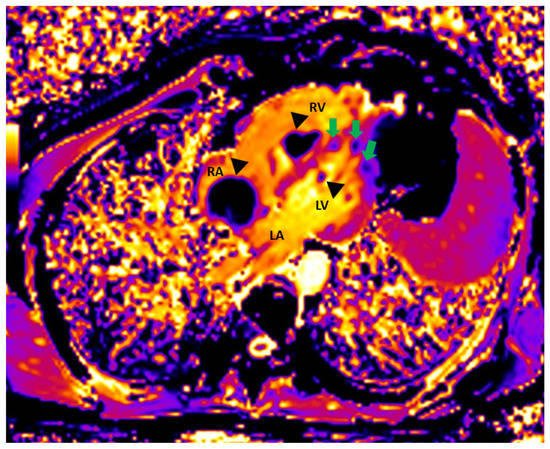

Figure 1. Initial scan: Transthoracic echocardiogram images, four chamber apical view (A,B) and parasternal long axis view (C,D). Multiple masses in the cardiac chambers are marked with black asterisks. A 30-year-old Caucasian man with a history of an in-situ melanoma of the forehead, which was surgically excised four years earlier, was referred for cardiac evaluation because of tachycardia and elevated levels of serum troponin. The patient had presented three months ago to the oncology clinic, with dry cough and pigmented skin nodules on the left shoulder, left forearm, chest, and forehead. Abdominal and brain computed tomography (CT) scans showed several metastatic lesions in the liver, the spleen, and the brain, while the histologic evaluation of one of the skin lesions revealed metastatic melanoma. Being BRAF-unmutated, the patient was initially treated with a combination of nivolumab and ipilimumab but due to grade 3 colitis, the treatment was replaced by a combination of dacarbazine and carboplatin. During clinical examination he was hemodynamically stable and his electrocardiogram showed sinus tachycardia at 120 beats per minute. The echocardiogram revealed multiple masses attached to the walls of both ventricles and the right atrium (RA) while no mass was detected in the left atrium (LA) (A). A large intracavitary mass (3.8 cm × 2.0 cm) was occupying almost one third of the right ventricle (RV) while a lobular right atrial nodule (2.4 cm × 2.2 cm) was attached to the posterior wall of the RA by a small peduncle (B,C). Additionally, a small mass in the left ventricle (LV) was attached to the interventricular septum (D). The end-diastolic RV volume was severely reduced by the mass, resulting in compensatory tachycardia, while there was no significant tricuspid valve inflow obstruction. The biventricular function was mildly reduced. A cardiac magnetic resonance (CMR) imaging confirmed the multifocal myocardial infiltration and the intracavitary masses and excluded the presence of thrombus in any of the cardiac chambers (Figure 2). Diffuse metastatic involvement precluded surgical management. One month later the cardiac metastases in RA and LV were unchanged on echocardiogram, while the tumor in RV was enlarged occupying the majority of the chamber, resulting in further reduction of the cardiac output and tachycardia (Figure 3, Supplemental Video S1). The treatment was changed to a combination of dacarbazine and carboplatin, but the patient eventually died two months later. Our case illustrates a rarity of metastasis of a malignant melanoma of to the heart providing useful information for doctors in training and practitioners. Melanoma is a skin malignancy with increasing incidence during the last decades and one of the most common cancers in young adults [1]. While it is responsible for less than 5% of all cutaneous malignancies, it is potentially lethal accounting for the majority of skin cancer deaths. Although, cardiac melanoma metastases are rare, with multichamber involvement being even rarer, there is a higher propensity of cardiac metastases typically by a hematogenous route compared with other tumors. However, despite that cardiac involvement is present up to 50% based on autopsy findings, including myocardial or pericardial infiltration, pericardial fluid, and intracavitary masses, metastases to the heart are usually clinically asymptomatic or present with nonspecific symptoms including cough, tachycardia, and dyspnea, making ante mortem diagnosis and treatment much more difficult [2,3]. Multimodalidy imaging, such as echocardiography, cardiac CT, but mostly, CMR due to its ability to differentiate tumor from thrombus, plays a pivotal role in the diagnostic work up [3,4]. Transthoracic and transesophageal echocardiography provide useful information about the morphology, the location and the vascularity of the tumor using contrast agent, as well as cardiac anatomy and physiology. Although, several morphologic features have been described on CT or CMR to differentiate benign from malignant cardiac lesions, their specificity are rather low. Contrast-enhanced CT is helpful in tumor staging because of its ability to detect extracardiac metastases, while a more accurate evaluation of the size of the tumor and its relationship to the adjacent tissues can be extracted by 3D reconstructed images. Furthermore, CT in conjunction with positron emission tomography (PET) enables both locating the tumor and providing information about the metabolic activity of the cardiac masses. PET can differentiate benign from malignant cardiac tumors, with the latter showing high 18F-fluorodeoxyglucose uptake. Lastly, tissue characterization and myocardial infiltration can be provided on T1 and T2 weighted and late gadolinium enhancement CMR images. Cardiac melanoma is usually demonstrated hyperintense on T1 and hypointense on T2-weighted imaging compared to the adjacent myocardium. Melanin-rich melanomas and mitral annular calcification show relatively short T1 times [5]. Conversely, thrombi and myxomas show intermediate and relatively long T1 times, respectively, while pericardial cyst shows the longest T1 time. The relatively low T1 values (~700 ms) of the melanin-rich metastatic foci on the corresponding T1 map can identify the myocardium studded with tumor. Metastases to the heart from melanoma indicate an advanced stage disease with poor prognosis and are typically accompanied by widespread metastases in other organs such as the liver, the lung, and the brain. In these cases, chemotherapy and immune checkpoint inhibitors should be considered as first-line therapy, while in BRAF-mutated cases, targeted therapy is also an option. However, in highly selected cases with solitary cardiac metastasis, if complete surgical resection of the cardiac mass with tumor-free margins from the atria or the ventricles is feasible, surgery can be considered as a therapeutic option, with survival up to one year in some case reports [6]. Nevertheless, the benefit outcome from these surgical procedures remains unknown due to the lack of longitudinal data.